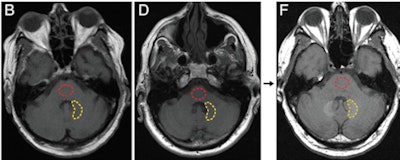

McDonald and colleagues imaged the deceased patients' entire brains using 1.5-tesla MRI, with an unenhanced T1-weighted axial sequence. They also assessed the subjects' renal function before each MR exam by using the estimated glomerular filtration rate (eGFR) derived from serum creatinine results taken within 24 hours of MRI.

As expected, the researchers found no detectable levels of gadolinium among the control subjects. However, there were elevated levels of gadolinium in four regions of the brain -- the dentate nucleus, pons, globus pallidus, and thalamus -- in the contrast subjects, ranging from 0.1 to 58.8 micrograms of gadolinium per gram of tissue.

The dentate nucleus contained the highest median concentration of gadolinium (6.6 micrograms per gram of tissue), while the pons had the lowest median concentration (0.3 micrograms per gram of tissue). The globus pallidus had 1.7 micrograms and the thalamus had 0.5 micrograms, the researchers found.

There were also moderate to strong correlations between T1-weighted MR signal intensity changes and tissue concentrations of gadolinium in all four brain regions, according to the group. This ranged from a Spearman rank correlation coefficient of 0.49 (p = 0.08) in the globus pallidus to 0.89 (p < 0.0001) in the dentate nucleus.